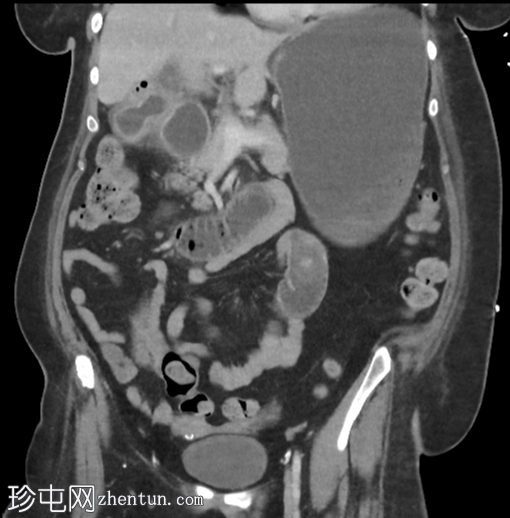

CT

矢状位增强扫描(门静脉期)

胆结石引起的高度小肠梗阻(胆结石性肠麻痹)

胆结石已侵蚀穿过胆囊壁进入十二指肠,形成胆囊十二指肠瘘

胆囊壁增厚,胆囊周围脂肪浸润,符合并发胆囊炎的影像学表现。胆囊窝内可见游离气体,但其他部位未见游离气体

胆囊颈或胆囊管内嵌顿胆结石